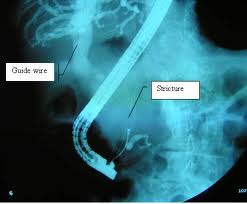

Devices that treat the circulatory system, including both cardiac and peripheral vascular devices

- Billiary catheters